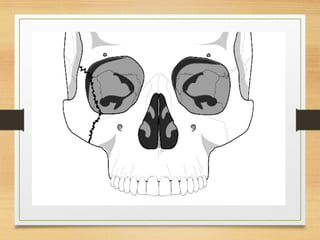

• Fracture lines usually run through the infraorbital rim

involve the posterolateral orbit and extend to the inferior

orbital fissre

• The fracture line then continues to the zygomatico sphenoid

suture area and on to the frontozygomatic suture line